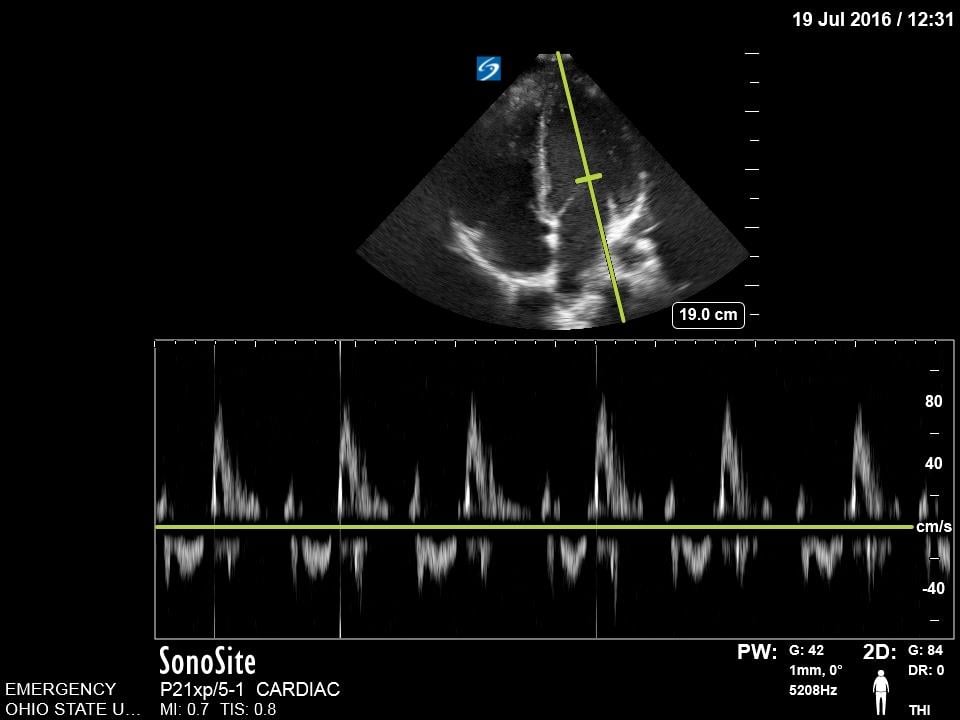

Mitral Valve Inflow

The mitral valve inflow is obtained by placing the pulse wave doppler gate at the tip of mitral leaflets in the apical four chamber view. In cases of suspected cardiac tamponade, a respiratory variability of greater than 25% is concerning for an exaggerated variation due to tamponade physiology.18 Although more advanced, this measurement can also be used for diastology.

Figure 14. Normal Mitral valve inflow on pulse wave doppler